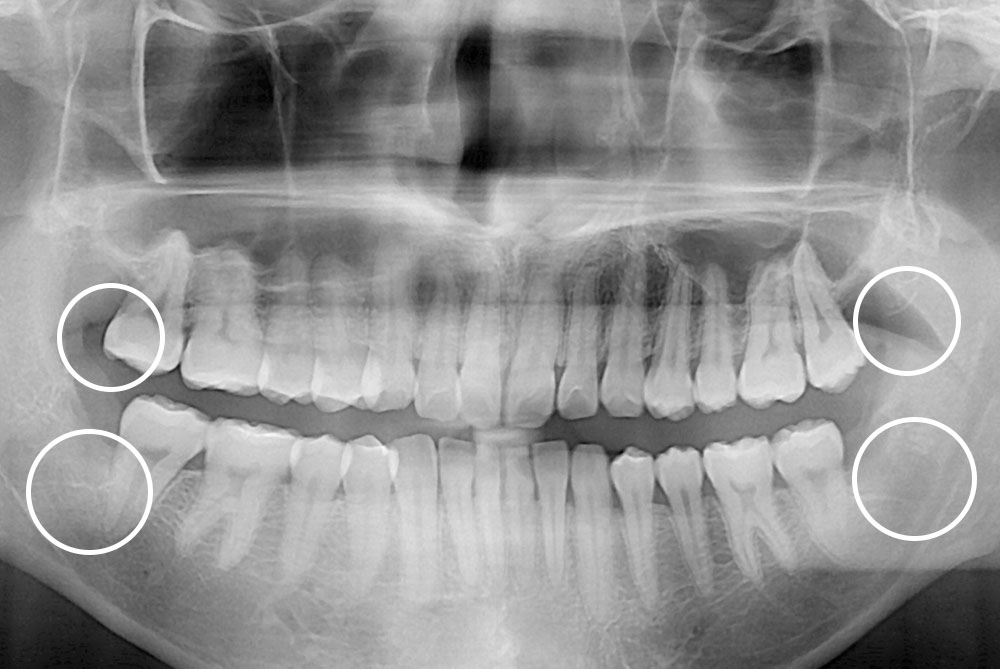

[사랑니] 매복 사랑니 발치

치료전 : 2020-03-26